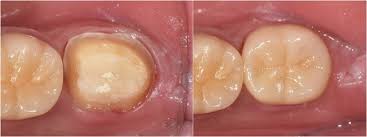

크라운은 손상된 치아 위를 씌우는 인공 보철물로, 치아를 외부 충격에서 보호하고 정상 기능과 자연 외형을 회복시켜 줍니다. 어금니는 내구성, 앞니는 심미성을 고려해 재료를 선택하는 것이 핵심입니다.

| PFM | 내부 금속 + 도재 | 내구+심미 균형 | 시간 지나 금속 노출 | 앞니·어금니 |

- 어금니: 내구성과 적합성 중요 → 골드, PFM, 메탈